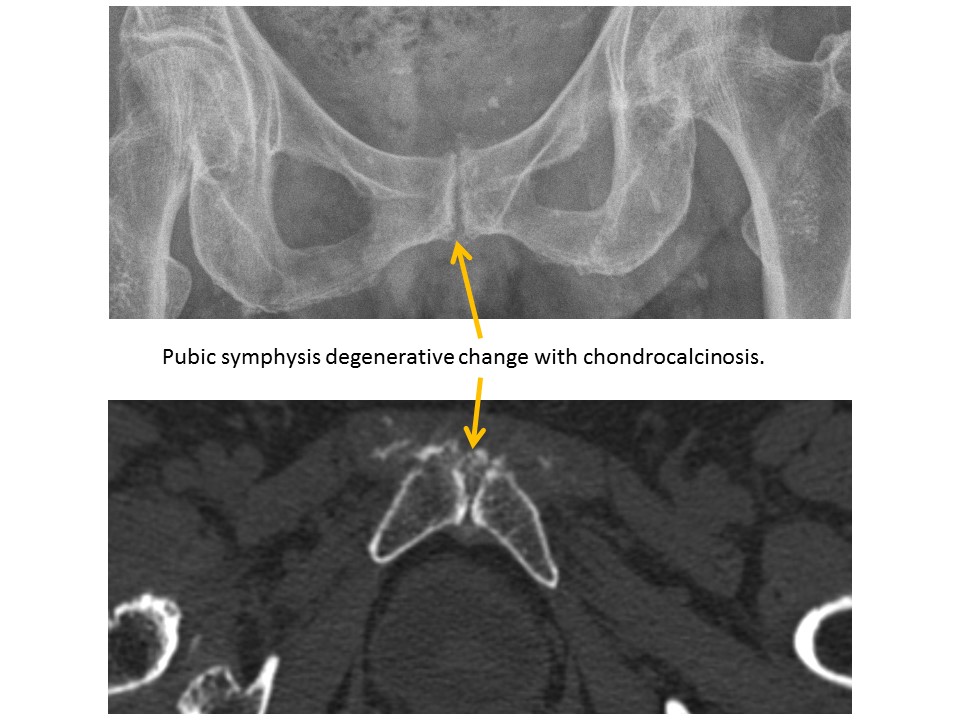

PUBIC SYMPHYSIS

The pubic symphysis is widened or vertically incongruent. [Yes/No]

There are CT findings of pubic symphysis inflammation or degeneration. [Yes/No]